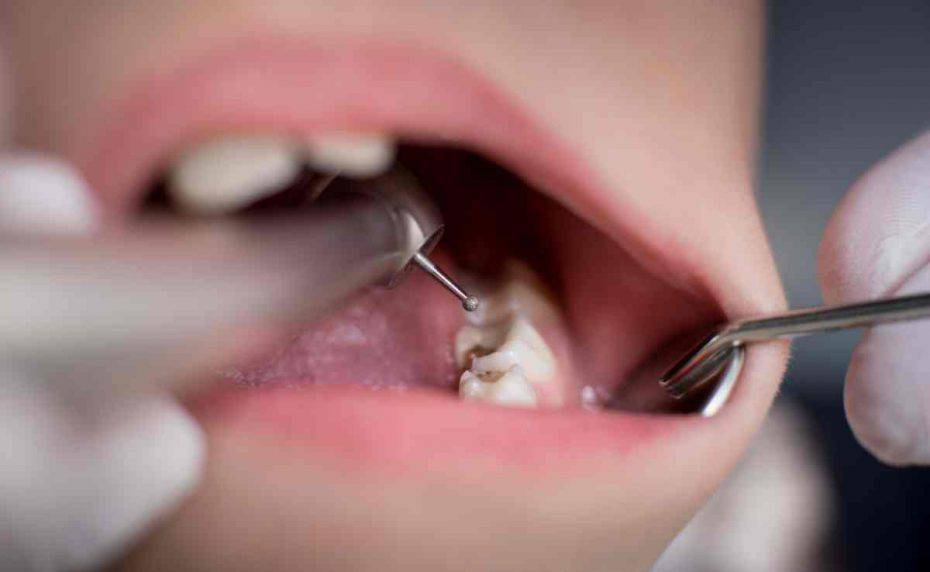

La carie si verifica quando l’acido viene prodotto dalla placca e poi si accumula sui denti danneggiandone la superficie. Ecco dei consigli utili per evitare la carie.

Visita regolarmente il tuo dentista. Ogni sei mesi andrebbe fatto un controllo. Più lo fai più diventa facile.Evita le bevande gassate